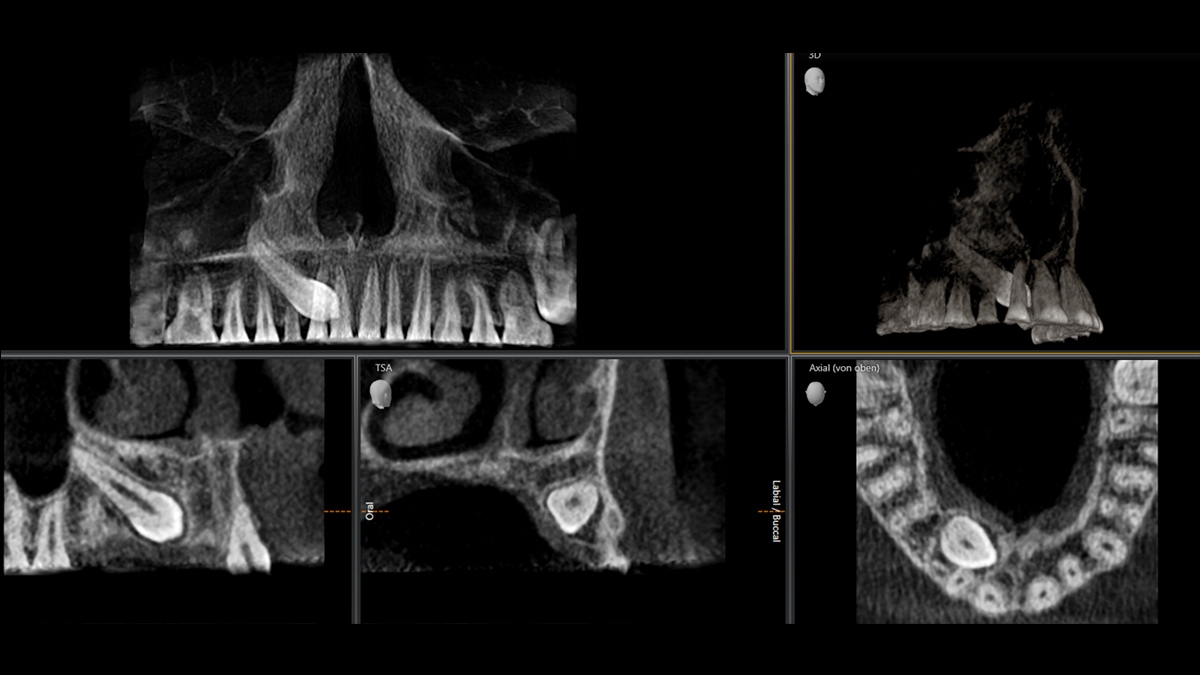

We developed a 10-point concept for easy patient positioning and X-ray imaging. Our concept is primarily about two things: high image quality and comfort for the patient and the assistant. This concept supports and provides the tools needed to ensure high-quality images for treatment analysis and focuses on ergonomics and comfort for the patient and assistant. The patented bite block technology, for example, automatically establishes the correct inclination of the patient's head, positioning the patient in the occlusal plane, partnering with the 3 point head fixation and firm handles to ensure stable positioning-limiting unnecessary correction scans.